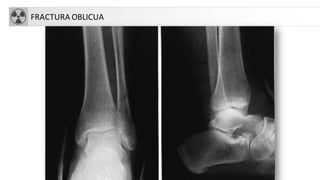

FRACTURA OBLICUA

FRACTURASDE TOBILLO

• Fracturas en supinación-rotación externa (60%)

• Fracturas en supinación-aducción (20%)

• Fracturas en pronación-rotación externa y pronación-

abducción (20%)

• Fracturas en pronación-dorsiflexión.

• A. Fractura unimaleolar (de tibiao

peroné)

• B. Fractura bimaleolar

• C. Fractura equivalentebimaleolar

• D. Fractura trimaleolar

• TratamientoQuirúrgico: En lesiones

de dos complejos, fracturas

inestables o desplazadas. Resto: tto

conservador